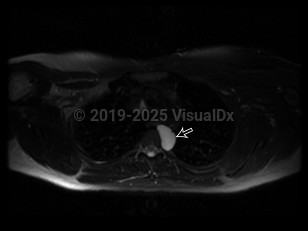

A bronchogenic cyst is a congenital respiratory tract malformation arising as an embryonic out-pouching of the foregut or trachea. Bronchogenic cysts can be found anywhere along the tracheobronchial tree and are often asymptomatic unless they become infected. Cysts typically appear as sharply marginated, water-density lesions on chest x-ray and may contain air-fluid levels when infected.